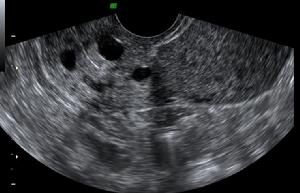

納博特囊腫超聲圖像示:

(1)本組彩色都卜勒顯示宮區宮旁血流豐富。

(2)本組液性暗區最大直徑18mm,最小直徑5mm,伴有子宮肌瘤7例(占14%),卵巢囊腫5例(占10%),盆腔積液10例(占20%),輸卵管積水2例(占4%),子宮次切術後1例(2%)。

(3)子宮頸肥大18例(占37%)。宮頸厚度在30mm以上,個別達到36mm。部分宮頸回聲可增強。

(4)頸部可見單或多個圓形或橢圓形液性暗區。單發19例(占39%),多發30例(占61%),邊界清晰,後方均伴有增強效應,其中5例還伴有囊壁鈣化。

分析:陰道超聲能彌補婦檢的不足,而且其對檢查者又具有操作簡便、診斷準確、針對性強、無創傷等優點。本組聲像圖具有一般囊腫聲像圖特徵,但其也應與子宮頸肌瘤等相鑑別。在聲像圖上子宮頸肌瘤為低回聲,CDFI示可有包膜血流,無囊腫特有的後壁增強效應。總之,陰道彩超能及時準確地查出已婚婦女的宮頸腺體囊腫,為臨床診斷及治療慢性宮頸炎提供了可靠依據宮頸腺體囊腫為宮頸慢性炎症所致,而臨床醫師僅能觀察到宮頸外口表面的小囊腫,但陰道彩超能查出宮頸深部腺體內所發生的瀦留性囊腫。納氏囊腫本身不引起患者自覺症狀,故未引起患者及臨床醫師的重視。隨著人們生活水平的提高,保健意識的增強;自從超聲診斷儀出現,體檢的婦女逐漸增多。上述49例均為體檢者,其中有宮頸炎的31例,有宮頸肥大18例,大致符合納氏囊腫的病因及病理。